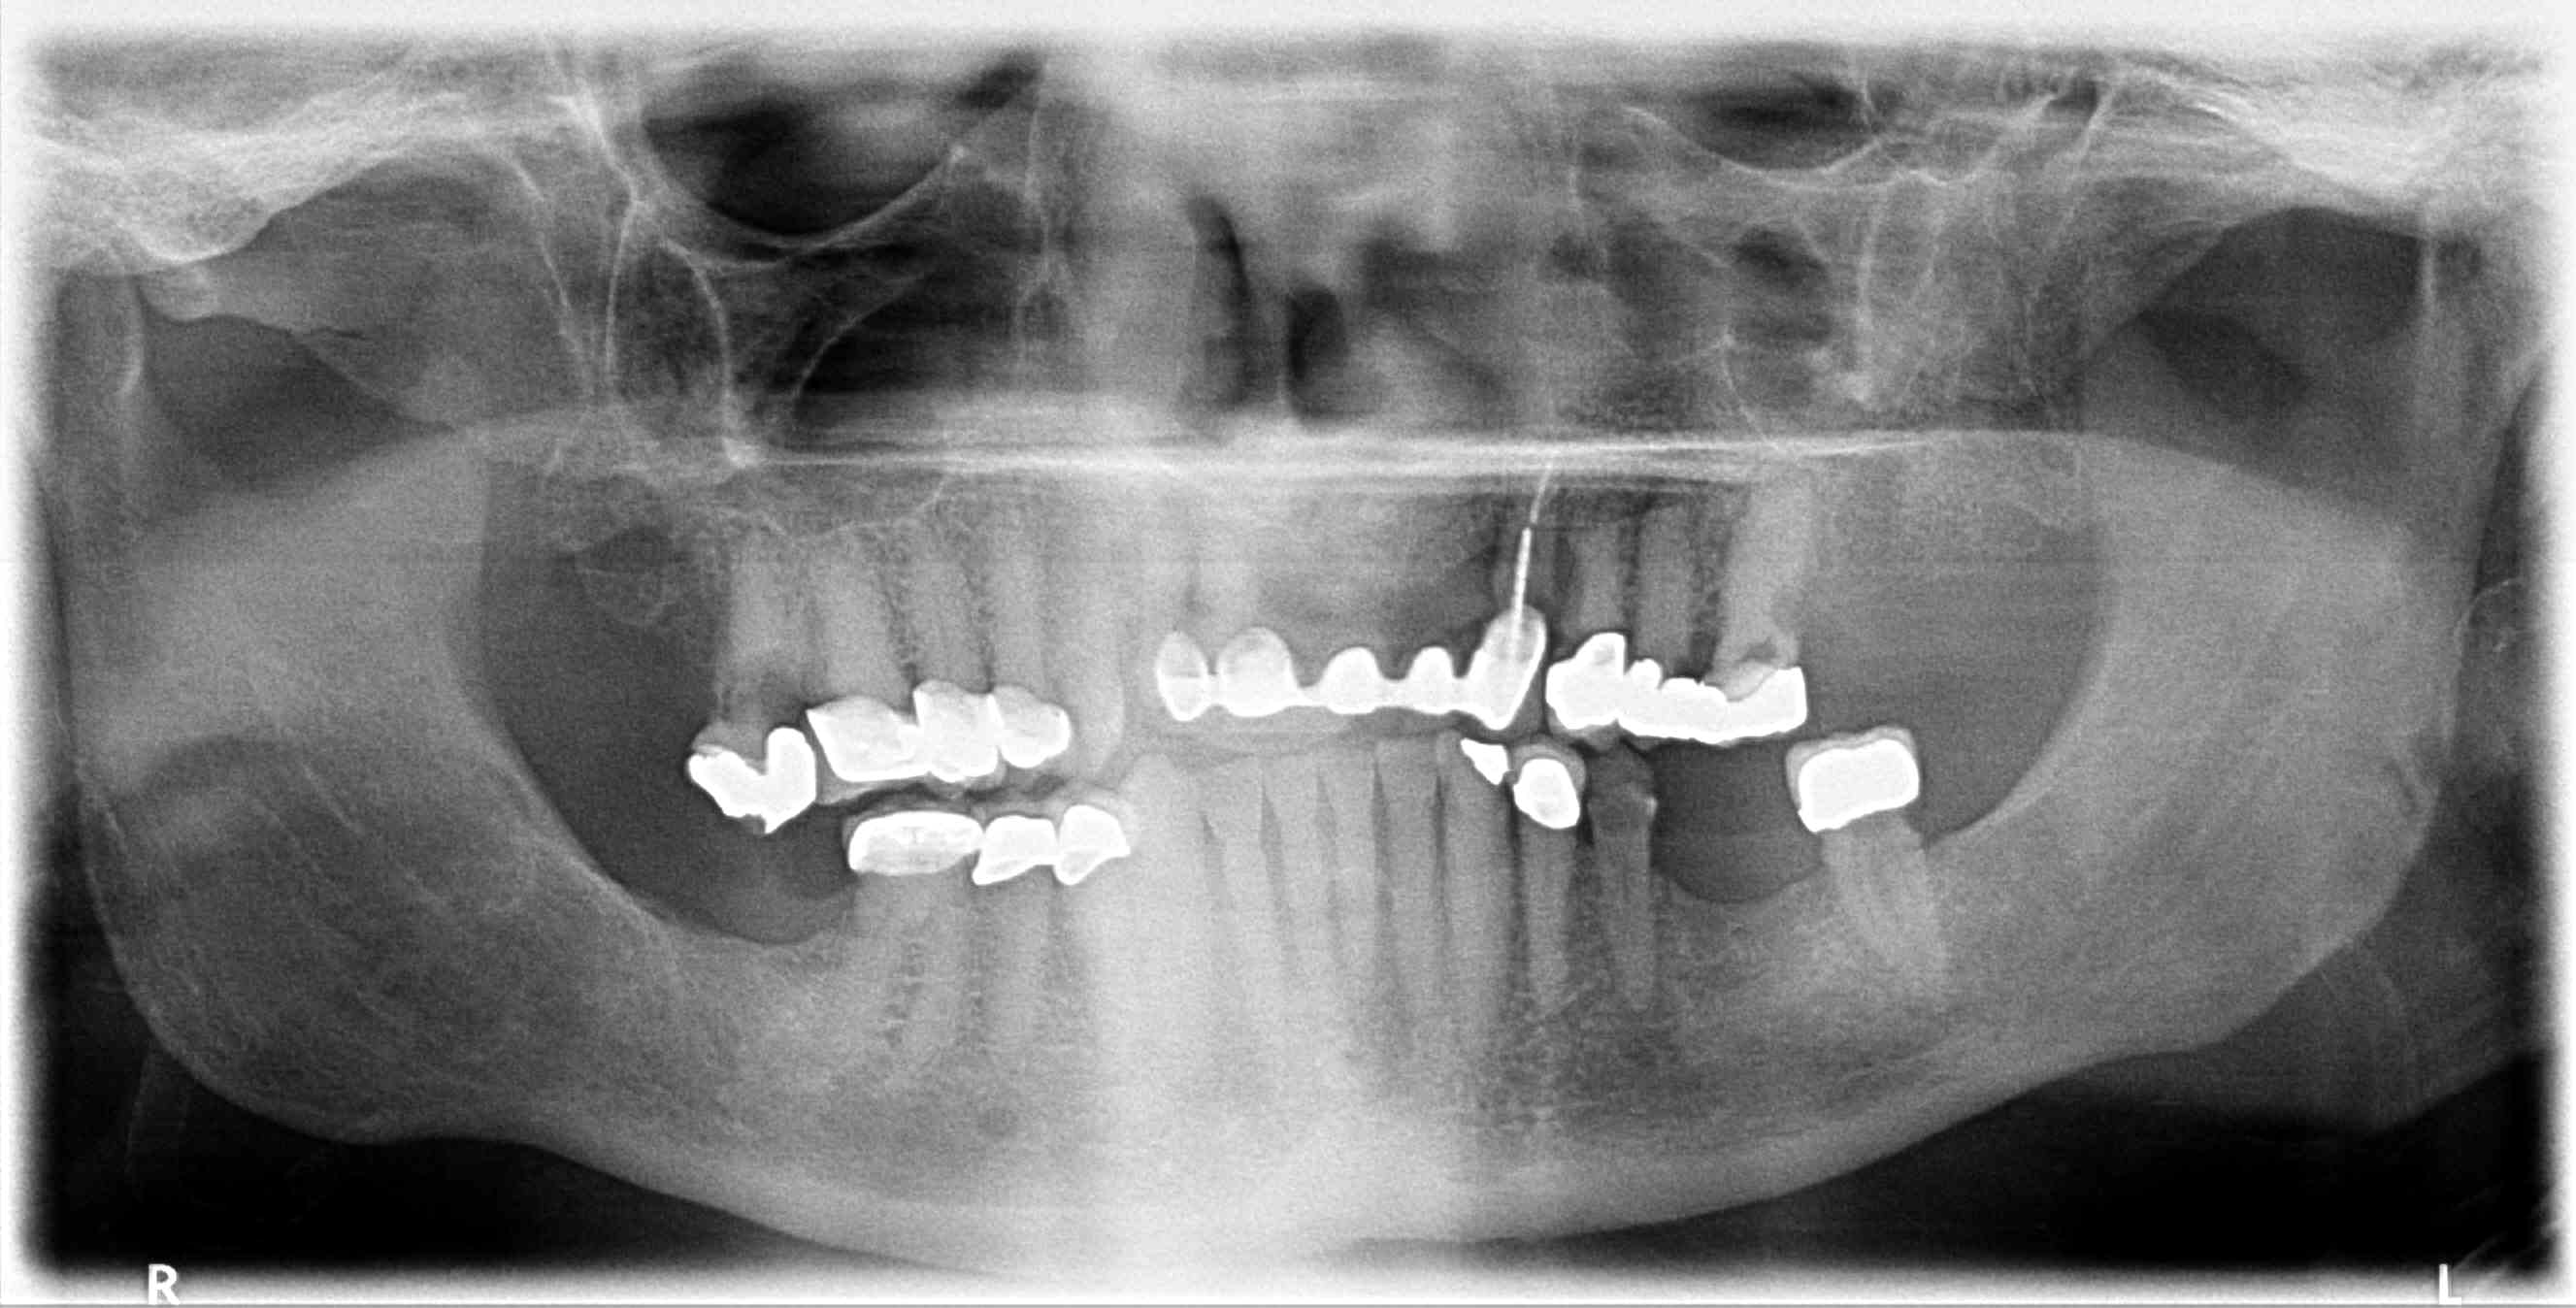

Patient requests ALL ON 4 for both upper and lower arches, complete case fee. X-rays available, taken last week

Auction images